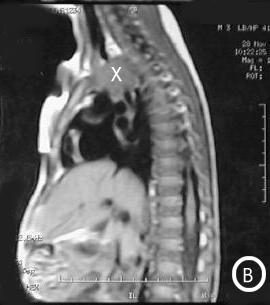

Resonancia Magnética

Corte longitudinal antero-posterior:

• Foto A: Corte longitudinal antero-posterior a la izquierda de la traquea. (X) = Masa mediastinal antero-superior en su extensión lateral izquierda de la traquea.

• Foto B: Corte longitudinal antero-posterior a la derecha de la traquea: (X) Masa mediastinal antero-superior en su extensión lateral derecha traqueal.

Corte trasversal detrás de la traquea.

• Foto C: (X) = el extremo derecho de la masa mediastinal.